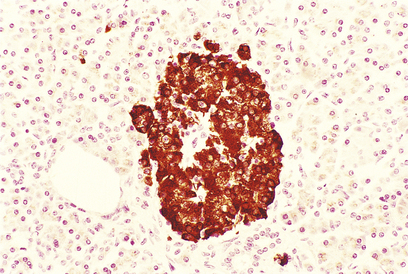

The islets consist of clusters of compact cells interspersed with small blood vessels (Fig. 17.41); they contain at least four distinct cell types, classified according to their hormone content as demonstrated by immunohistochemistry (Fig. 17.42).There are regional differences in hormone content of the islet cells in different parts of the pancreas, but the average hormonal composition is as shown in Table 17.9.

image

Fig. 17.42 Beta-cells in an islet of Langerhans. This normal pancreas has been stained by the immunoperoxidase technique for insulin. The insulin-containing cells are darkly stained.